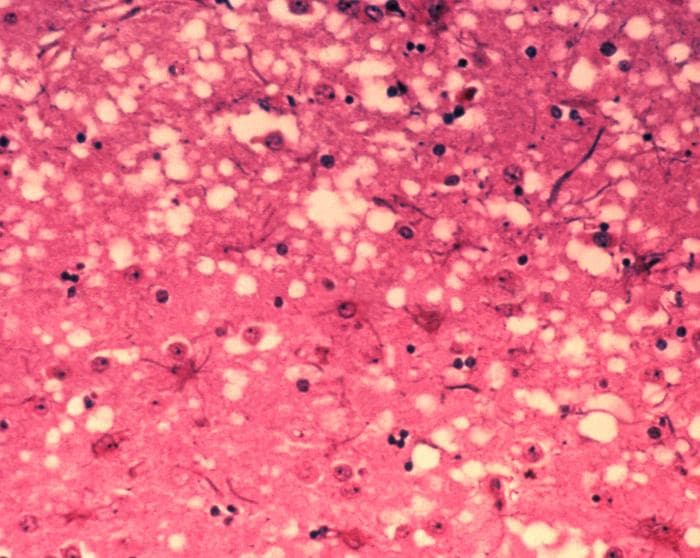

Transmissible spongiform encephalopathies (TSEs) also known as prion diseases, are a group of progressive, incurable, and fatal conditions that are associated with prions and affect the brain and nervous system of many animals, including humans, cattle, and sheep. According to the most widespread hypothesis, they are transmitted by prions, though some other data suggest an involvement of a Spiroplasma infection. Mental and physical abilities deteriorate and many tiny holes appear in the cortex causing it to appear like a sponge when brain tissue obtained at autopsy is examined under a microscope. The disorders cause impairment of brain function, including memory changes, personality changes and problems with movement that worsen chronically. TSEs of humans include Creutzfeldt–Jakob disease, Gerstmann–Sträussler–Scheinker syndrome, fatal familial insomnia, and kuru, as well as the recently discovered variably protease-sensitive prionopathy and familial spongiform encephalopathy. Creutzfeldt-Jakob disease itself has four main forms, the sporadic (sCJD), the hereditary/familial (fCJD), the iatrogenic (iCJD) and the variant form (vCJD). These conditions form a spectrum of diseases with overlapping signs and symptoms. TSEs in non-human mammals include scrapie in sheep, bovine spongiform encephalopathy (BSE) in cattle – popularly known as "mad cow disease" – and chronic wasting disease (CWD) in deer and elk. The variant form of Creutzfeldt–Jakob disease in humans is caused by exposure to bovine spongiform encephalopathy prions. Unlike other kinds of infectious disease, which are spread by agents with a DNA or RNA genome (such as virus or bacteria), the infectious agent in TSEs is believed to be a prion, thus being composed solely of protein material. Misshapened prion proteins carry the disease between individuals and cause deterioration of the brain. TSEs are unique diseases in that their aetiology may be genetic, sporadic, or infectious via ingestion of infected foodstuffs and via iatrogenic means (e.g., blood transfusion).